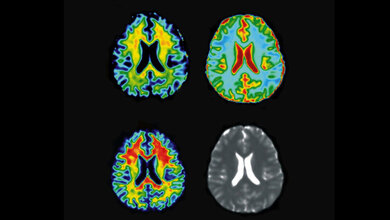

Methodik der doppelt diffusionsgewichteten Kernspintomographie

Patricia Ulloa, Doktorandin aus Chile, erhielt einen „Certificate of Merit Award“ für ihren Beitrag „Water-in-oil emulsion as a simple phantom for validation of double diffusion encoding MRI sequences“ zur Methodik der doppelt diffusionsgewichteten Kernspintomographie. Ziel ihrer Arbeiten ist es, neue nichtinvasive Wege der Beurteilung der Gewebestruktur zu finden, die es ermöglichen, pathologische Veränderungen aufzuspüren. Solche Methoden haben den Vorteil, dass sie Informationen über mikroskopische Strukturen liefern, deren Größe weit unterhalb der eigentlichen Ortsauflösung der kernspintomographischen Bilder liegt. Der ausgezeichnete Beitrag stellte ein Messphantom her, das sich durch seine mikroskopische Struktur zur Validierung solcher Messungen eignet.